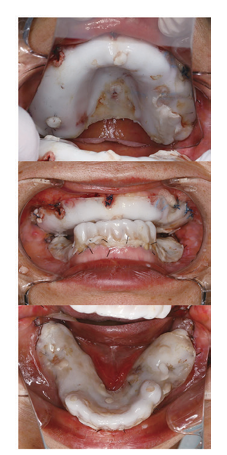

上顎残存歯はすべて抜去とし、十分なデンチャースペースを確保できるように研究用模型上でモデルサージャリーを行い、術後の口腔内を想定した。このモデルサージャリーを手術中の口腔内に再現できるように、アクリル製熱可塑性シートを用いてサージカルガイドを製作し、全身麻酔下において上顎抜歯術および骨隆起形成術を施行した。術後、創部の治癒が良好であることを確認し、上顎に全部床義歯、下顎に部分床義歯を装着した。その後、問題なく義歯を使用している。

<サージカルガイドを流用し装着した、シーネ>

<術後の義歯装着写真>